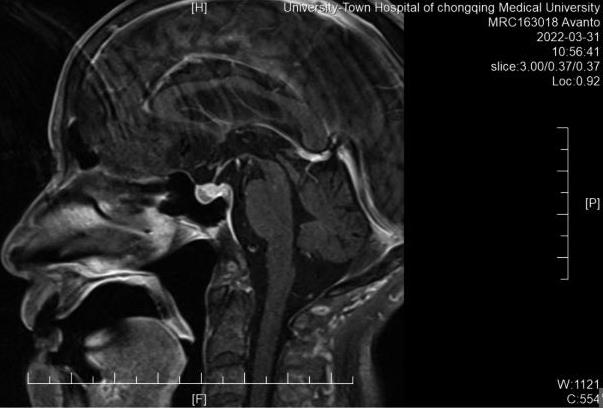

• 长效生长抑素类似物治疗垂体促甲状腺激素腺瘤1例并文献复习

2023, 48(9):1116-1121. DOI: 10.13406/j.cnki.cyxb.003336

摘要 (120) HTML (37) PDF 677.52 K (209) 评论 (0) 收藏

摘要:

• 0+1

• 1+1

• 2+1